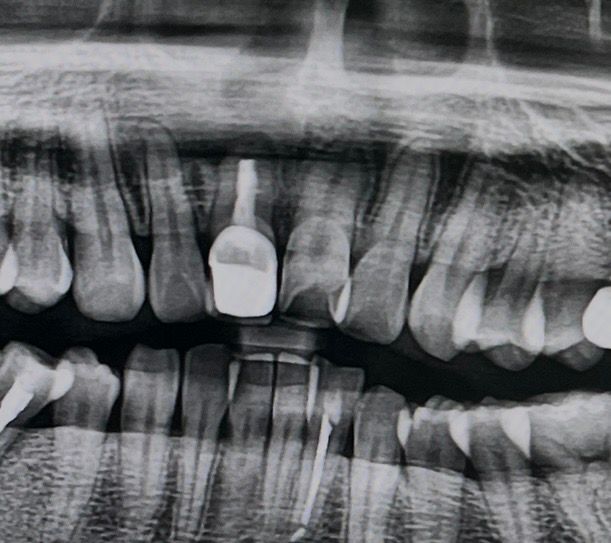

치아 뿌리 염증? 물혹? 씨티 좀 봐주세요ㅡ ㅜㅠ

개인 병원에 갔는데 처음에는 엑스레이 상으로는 전신 마취 꼭 안하고 수술해도 된다 하셨어요

그런데 ct찍어보고는 대학병원 가야할 것 같다고 하네요…..

• 2번 째 사진